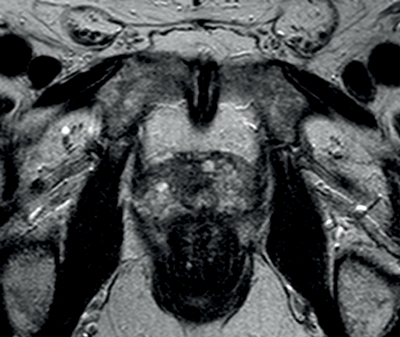

Transitional and central zone tumours are more difficult to evaluate using conventional T1 and T2WI as both normal and cancerous tissues in these areas demonstrate low signal intensity. Additionally, the normal central gland is commonly heterogeneous, making delineation of abnormal areas challenging. DWI may improve the detection and localisation of central / transitional zone tumours, as they also demonstrate restricted diffusion. Studies have shown that transitional zone tumours have lower ADC values than normal gland as well as BPH nodules [5,6] (Figure 2). The sensitivity for tumour detection in the transitional zone, however, still remains less than in the peripheral zone [5].

Figure 2a: Axial T2WI with low signal in the right central zone.

Figures 2b and 2c: DWI and ADC map confirm restricted diffusion at the site of tumour.